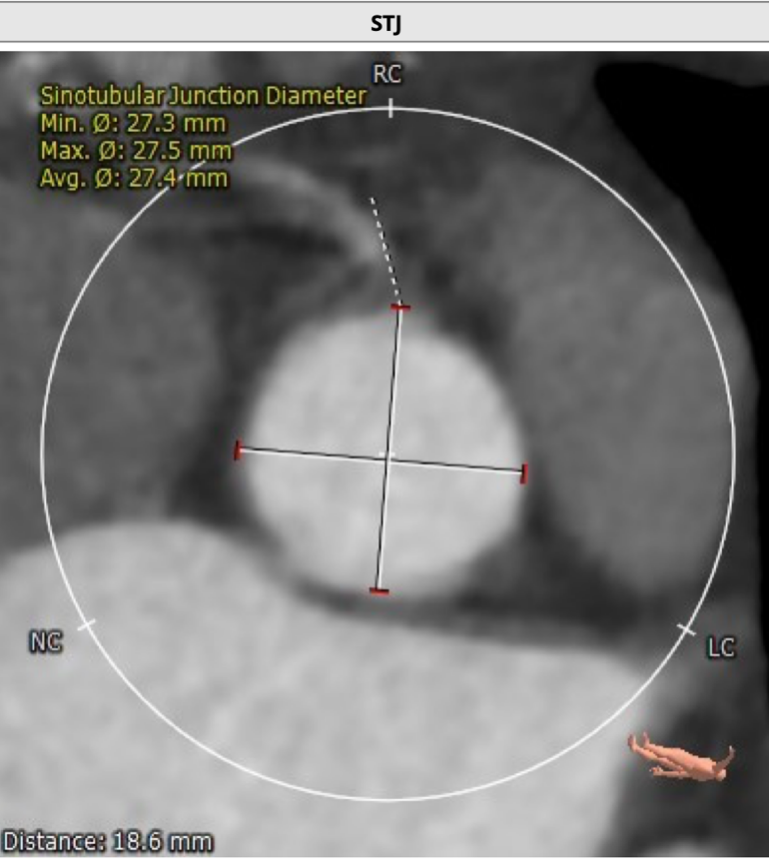

患者为73岁老年男性。CT评估显示其为三叶瓣,伴有轻度钙化,双冠高度可,升主动脉未见明显增宽,主动脉弓部角度平缓。瓣环最短径为17.6mm,最长径为24.7mm,平均瓣环直径为21.1mm。升主动脉平均直径33.6mm。左冠开口高度12.0mm,右冠开口高度14.2mm,冠脉阻塞风险低。外周血管未见明显钙化,最窄处直径为5.7mm。入路情况较佳。

窦管交界部